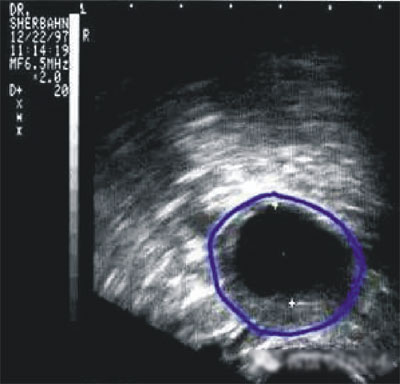

陰道B型超聲動態(tài)監(jiān)測卵泡的發(fā)育及排卵,是監(jiān)測排卵最準確可靠的方法。通過陰道B超檢查可以了解子宮及雙側(cè)附件(卵巢和輸卵管)區(qū)的基本情況,測定卵巢內(nèi)的竇卵泡計數(shù),評估卵巢儲備功能,動態(tài)監(jiān)測排卵。